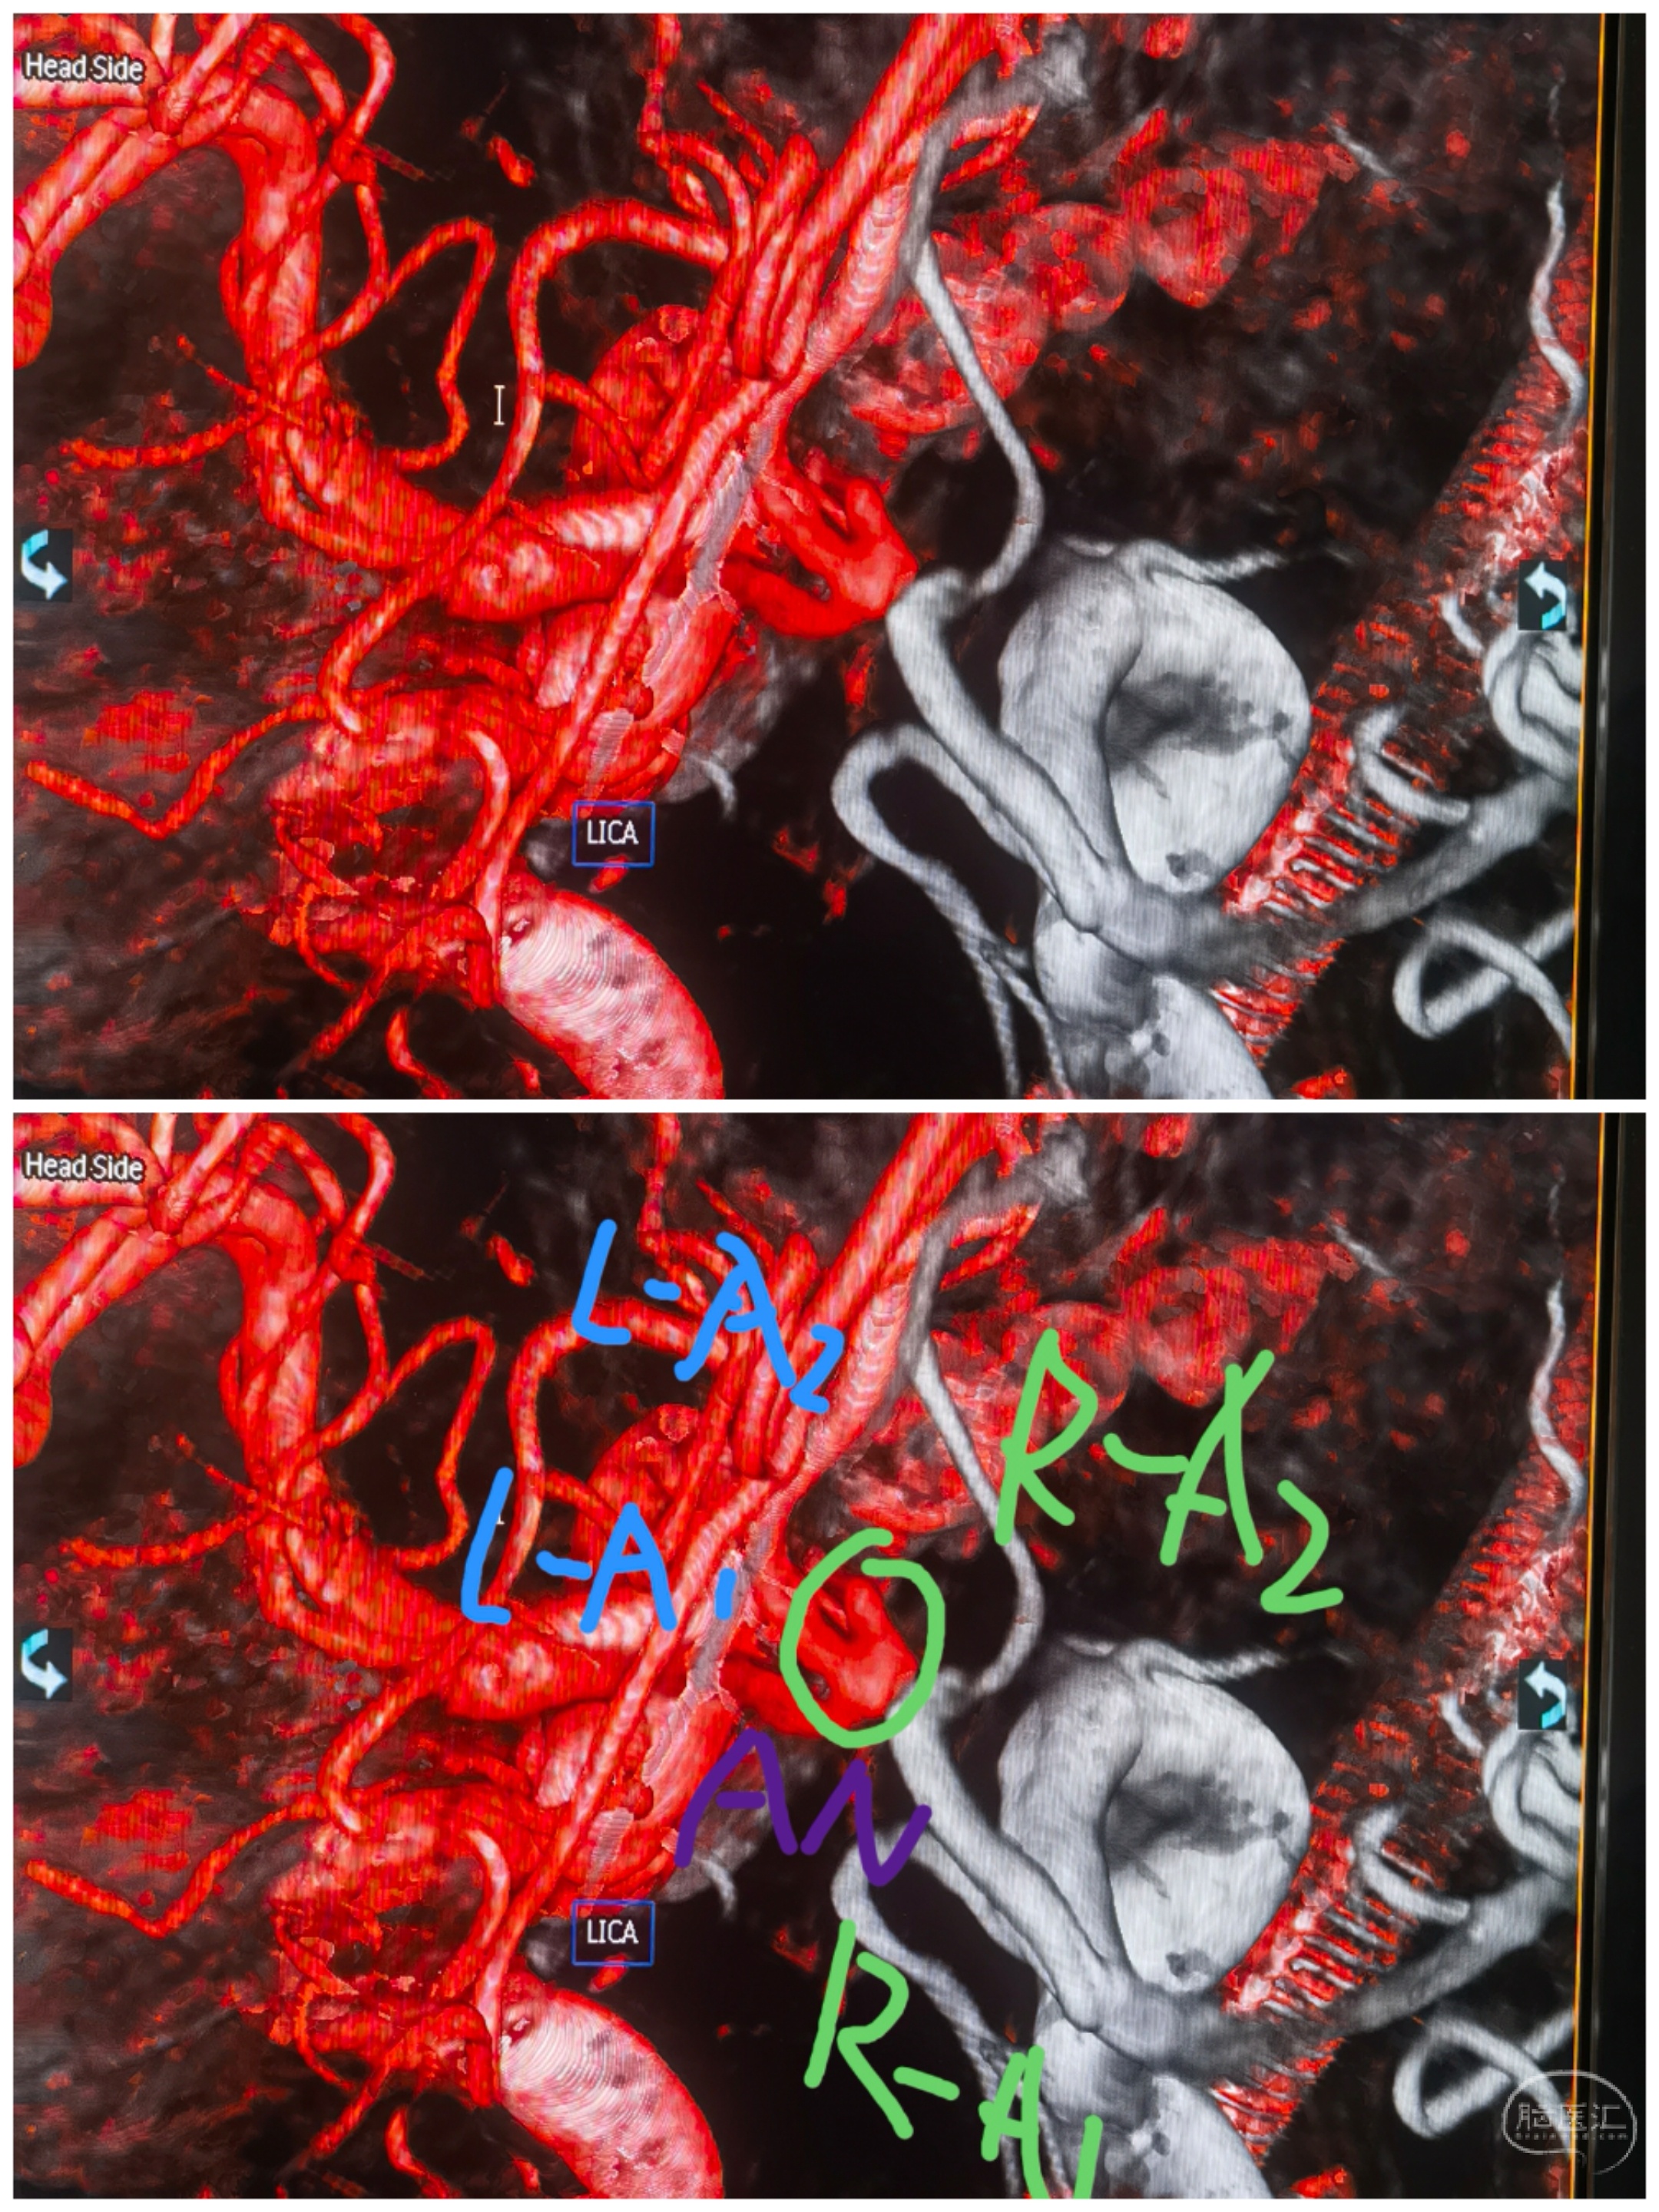

结构分析

最初手术计划:左侧大脑前优势,左颈内造影前交通动脉瘤显影。拟经左侧通路治疗,左侧A1-左侧A2释放支架导管,左侧A1释放栓塞微导管。无奈左侧A1-左侧A2夹角锐利,支架导管无法通过😂😂

还好术前龙哥远程指导提醒了下,可以经右侧A1-前交通-左侧A2走支架导管。果断更换思路,经右侧通路,双侧同时路途。经右侧A1-前交通-左侧A2支架导管,右侧A1栓塞导管直接指向动脉瘤。